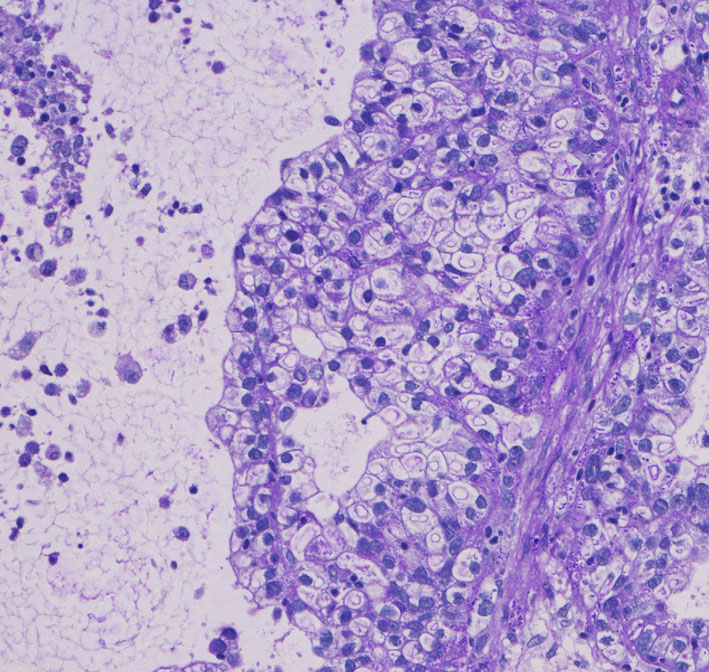

腫瘍中心の壊死の部分です。腫瘍細胞が死滅して凝固壊死の像です。血管はヒアリン化して閉塞しています。

腫瘍の辺縁部で手術中に血管が発達して出血があった部分です。腫瘍細胞 clear cell carcinoma が新生血管周囲に増殖しています。真ん中はPAS染色,右側はMIB-1染色で13%くらいの高い陽性率です。これは定位放射線治療で腫瘍が全部死滅していなくて一部では再発していることを示します。

さらに周辺と正常脳との境界部位です。脳組織が壊死になっていてます。放射線脳壊死が周囲にあって,高度の脳浮腫を生じていたことがわかりました。

この例は,定位放射線治療後に,1) ガン組織が壊死になって放射線治療の効果が認められる,2) ガン転移の再発がある,3) 放射線脳壊死が起こっている,という3つの事象が混じって生じているものです。ですから,PETやMRSなどで手術の前の画像診断を頑張ってみても,診断がつくはずがないのです。病理診断しか手段がありません。